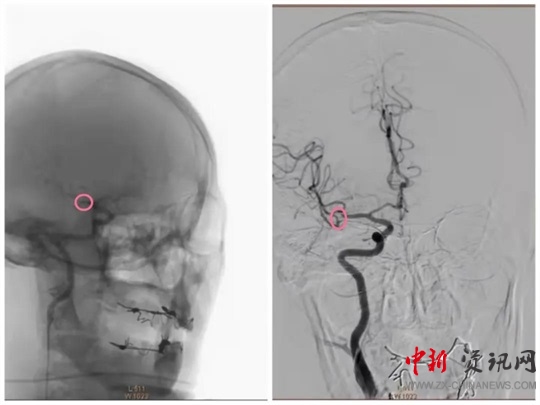

經(jīng)過一系列的術(shù)前準備并經(jīng)患者家屬同意后,立即繞行病房進入介入手術(shù)室,實施緊急手術(shù)。卒中中心團隊、胸痛中心團隊和介入團隊密切配合,為患者分別實施了腦動脈造影+主動脈弓造影+顱內(nèi)動脈瘤栓塞術(shù)+冠狀動脈造影術(shù)+經(jīng)皮冠狀動脈支架植入術(shù),成功把患者從死亡邊緣拉回。目前,患者病情穩(wěn)定,各項指標良好。

(動脈瘤栓塞前)